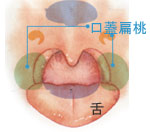

扁桃肥大(へんとうひだい)

口蓋扁桃が大きい状態です。

睡眠時の呼吸障害や、飲みづらい原因になることがあります。

扁桃炎(へんとうえん)

口蓋扁桃が大きい状態です。

睡眠時の呼吸障害や、飲みづらい原因になることがあります。